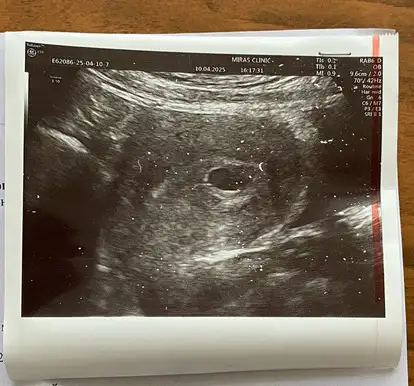

6 haftalık ve 8 haftalik yorumunuzu banada yapabilir misiniz